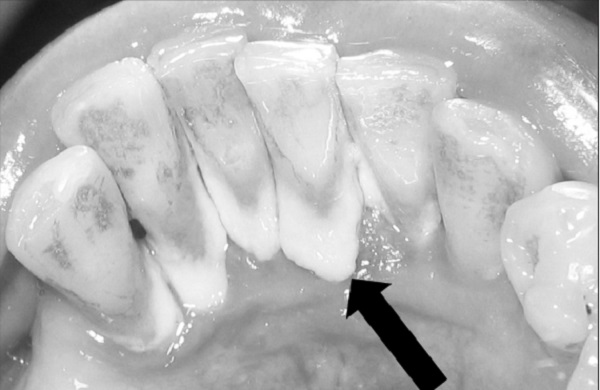

![]() |

| Mảng bám không được loại bỏ dẫn đến các bệnh răng miệng. |